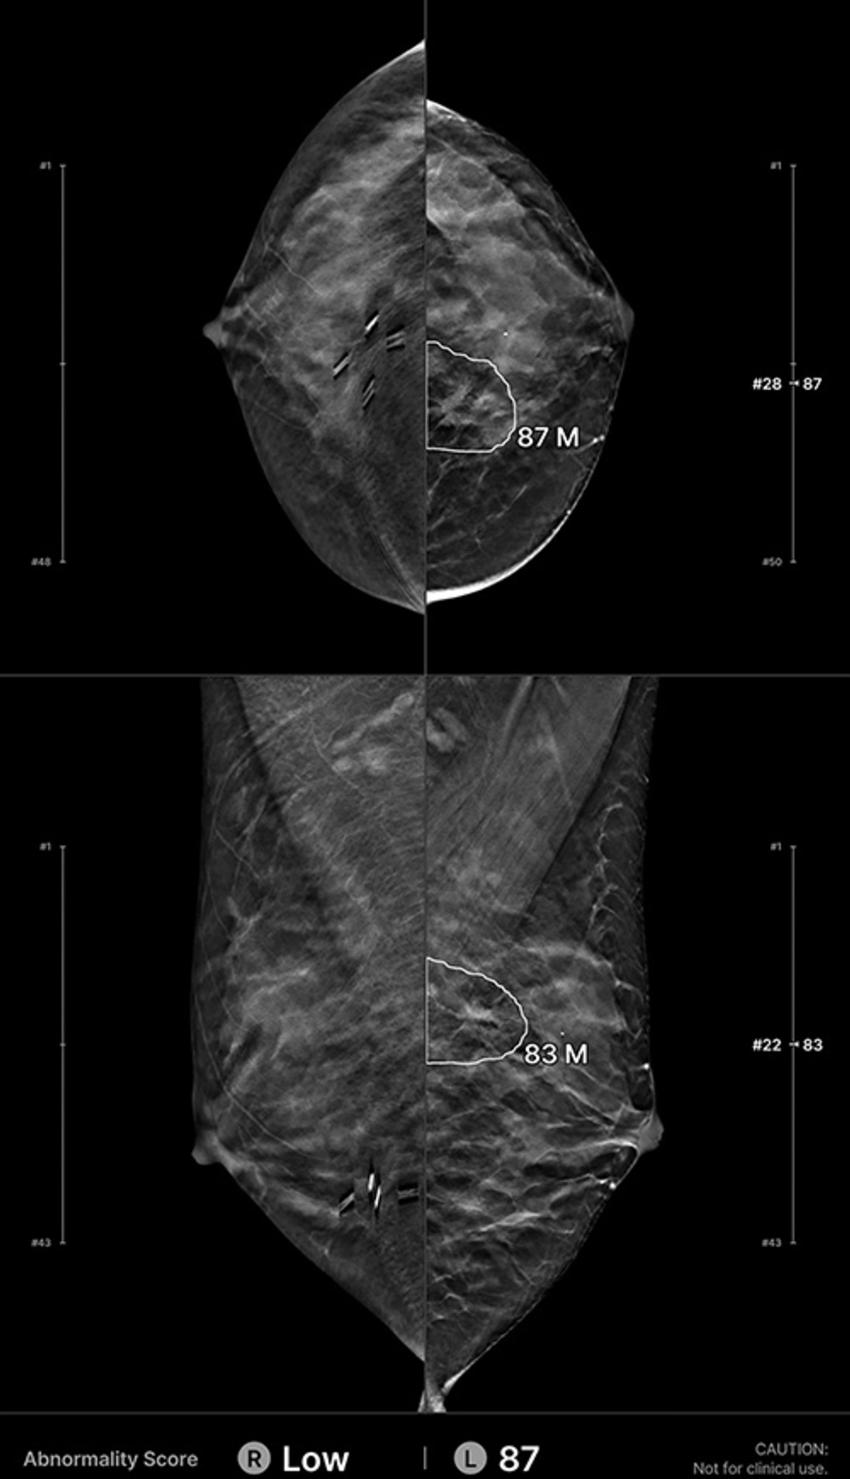

Figure 3. Example of an interval cancer retrospectively detected by the artificial intelligence (AI) algorithm. A 48-year-old woman presented for a screening digital breast tomosynthesis examination; its findings were interpreted as negative. Eleven months later, the patient presented with a lump in the left breast and was subsequently diagnosed with grade 1 invasive ductal carcinoma. At retrospective evaluation of the initial screening mammogram, the AI algorithm marked a suspicious lesion (white outline) in the left breast, with high scores of 87 on the craniocaudal view and 83 on the mediolateral oblique view. This mass with associated architectural distortion corresponds to the cancer that was subsequently diagnosed.